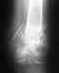

здравствуйте!подскажите,берут ли в армию с таким заключением врачей -"на серии МСКТ срезов стоп с последующей реконструкцией изображения отмечается снижение высоты суставной щели таранно - пяточных суставов обеих стоп, выраженный субхондральный склероз суставных поверхностей с наличием остеопериостозов в местах прикрепления связок. Кроме того, отмечается кистовидная перестрйка пяточных костей."

ЗАКЛЮЧЕНИЕ: МСКТ признаки посттравматического артроза таранно-пяточных суставов стоп 2-3 ст.